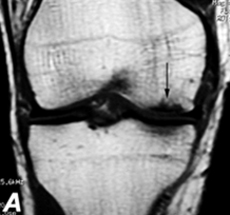

Necrosi del solo compartimento mediale del ginocchio con modesto varismo in paziente entro i 60 anni: ottima indicazione all'intervento di osteotoma di valgizzazione

Nei casi in cui vi sia una severa degenerazione della cartilagine di una sola zona del ginocchio (in genere quella interna) e vi sia associata anche una deformazione in varismo della gamba, in un paziente piuttosto giovane (in genere sotto i 60 anni), vi e' l'indicazione ad effettuare l'intervento di osteotomia della tibia c.d. di "valgizzazione". Tale intervento ha lo scopo ultimo di spostare il carico sul ginocchio dalla zona malata mediale o interna a quella sana laterale. Si tratta quindi, in definitiva, di un intervento "biomeccanico" ovvero un intervento che pur non utilizzando protesi artificiali o altri sistemi di rivestimento biologici, riesce comunque ad apportare un significativo miglioramento sia sul dolore sia sulla funzionalita' del ginocchio.